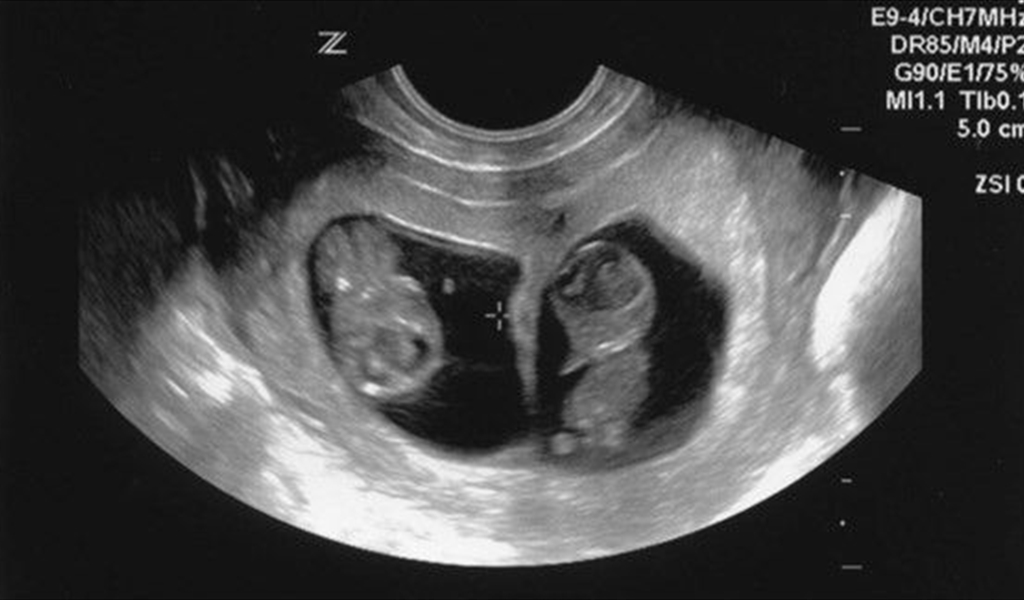

متى يظهر الحمل بتوأم في السونار المهبلي، من المعتاد أن تحمل المرأة في جنينها ولكن قد تحدث بعض الحالات التي تحمل المرأة في توأم أو أكثر، وهناك نوعان من التوائم الأول يكونان مختلفان لأن ذلك التوأم ناتج عن تلقيح بويضتان ويتواجد كل جنين منهما داخل كيس منفصل، أما النوع الثاني فيكون التوأم داخل نفس الكيس لأنهما ناتجان عن انشقاق بويضة، وفي السطور التالية من خلال موقعنا اراء نتعرف متى يظهر الحمل بتوأم في السونار المهبلي.

هناك بعض الحالات التي لا يظهر فيها التوأم في السونار العادي على البطن وخاصة في الأوقات المبكرة من الحمل، مما يضطرهن إلى اللجوء إلى السونار المهبلي، ففي أي وقت يظهر الحمل بتوأم في السونار المهبلي:

- أما في حالة استخدام السونار المهبلي، فيظهر التوأم في الأسبوع السابع إلى التاسع وذلك عبر السلي الذي يحيط بالتوأم في الرحم.

متى يظهر الحمل بتوأم في السونار المهبلي، يتيح السونار المهبلي معرفة وجود التوأم بداية من الأسبوع السابع في حين لا يكشف السونار العادي الأمر سوى في الأسبوع العاشر أي في الشهر الثالث.